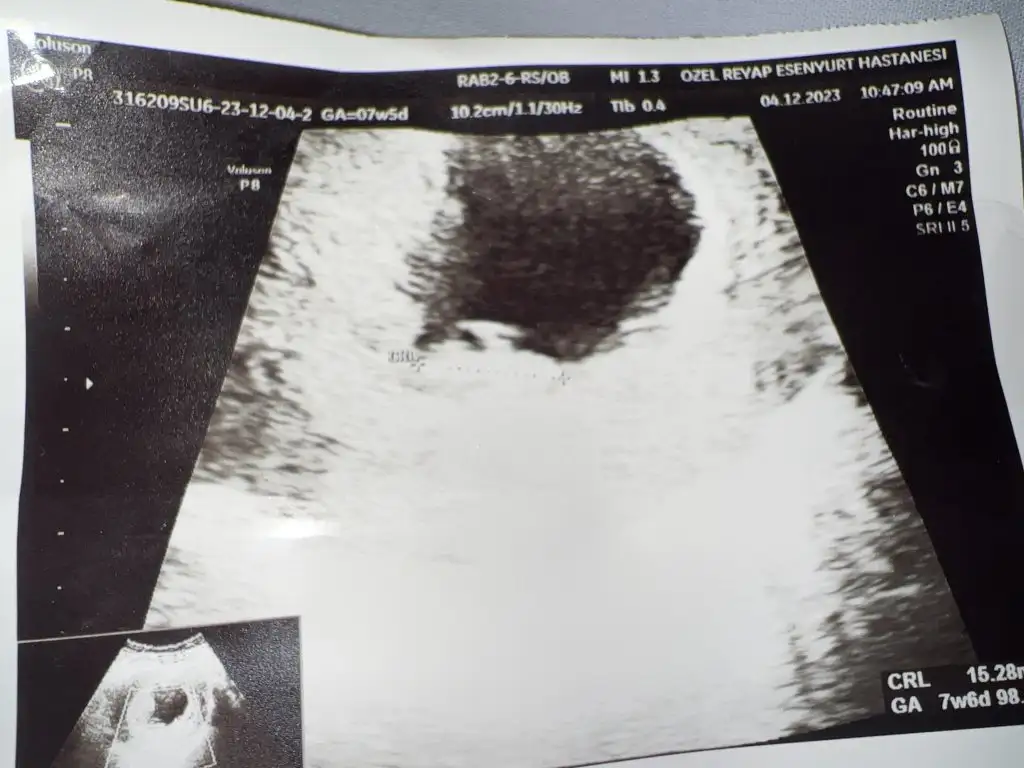

Merhaba cinsiyeti nedir bebeğinizinmerhaba keseden cinsiyet tahmini yapılıyormus 10. Hafta ultrason görüntümüz tahmini olan varmi

Bence keseye göre kız,yuvarlak çünkü benim üç gebeliğimdede kese yuvarlak değildi ve üçüde erkek

ben de cozmeye calısıyorum. kesem yuvarlak ama erkek yorumu yapmıslar yukarda baska forumlarda kese yuvarlaksa kız dıyorlar fasulyeye yakınsa erkek. bebek yeni olusmaya basladıgında sag taraftaysa kız soldaysa erkek.(hani bu kesenın icinde kucuk olusum oluyo ya yolksac o sanırım) ama doktor ulktrasonda aleti sag sol cevirebiliyor onu nerden bilcezzzzYorum gelsinde sağlıklı olsun önemli değilanlayanlar nerde hiç yazmıyorlar

Karın yada vajinalde farkediyormuş falan bir sürü şey var hayırlısı sağlıklı olsun ama insan merak ediyor 12 haftaya gelince bütün merakımız gidecek inşallah ama gerçekten anlayanlar var artık burda göre göre araştırıyorlar biliyolarben de cozmeye calısıyorum. kesem yuvarlak ama erkek yorumu yapmıslar yukarda baska forumlarda kese yuvarlaksa kız dıyorlar fasulyeye yakınsa erkek. bebek yeni olusmaya basladıgında sag taraftaysa kız soldaysa erkek.(hani bu kesenın icinde kucuk olusum oluyo ya yolksac o sanırım) ama doktor ulktrasonda aleti sag sol cevirebiliyor onu nerden bilcezzzz